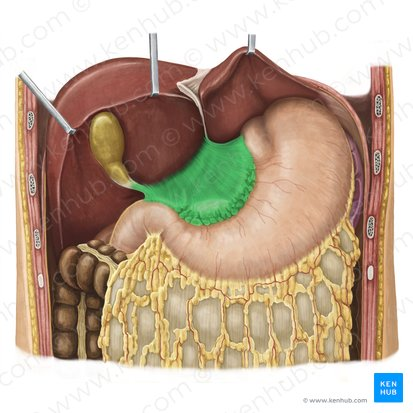

Liver

Lesser omentum

Hepatoduodenal ligament

blue box

Hepatogastric ligament

pink box

Greater omentum

Duodenum